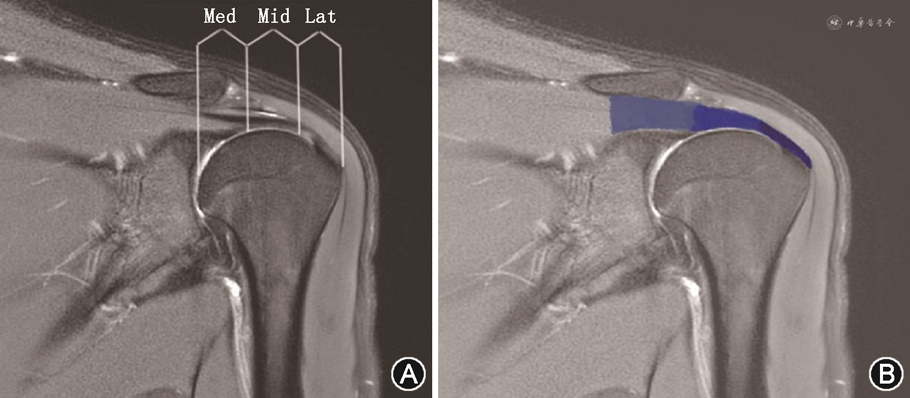

扫描完成后由2名具有10年以上骨肌系统疾病诊断经验的放射科医师独立阅片,使用GE主机定量磁共振图像编译(magnetic resonance image compilation,MAGIC)处理软件包进行图像后处理,生成 T1 mapping、T2 mapping 和 PD mapping 3组定量图谱。参照Ashir等[8]的研究方法,于T2WI斜冠状位图像上以肌肉-肌腱为单元根据肌腱的走形将冈上肌肌腱分为外侧亚区(指冈上肌肌腱纤维远侧插入区域)、中间亚区(指外侧亚区和内侧亚区连线的中点区域)及内侧亚区(指位于外侧亚区内侧方向2 cm左右、高于肱骨头软骨的区域),分别于肌腱的3个亚区勾画感兴趣区(region of interest,ROI),避开脂肪、积液及周围其他组织(图1)。ROI的勾画及测量分别由2名放射科医师(观察者1和2)独立完成,并在间隔至少2 周后重复测量数据,以评估观察者间和观察者内的一致性。最终的分析数据为2名医师4 次测量结果的平均值。

注:Mid为中间亚区;Med为内侧亚区;Lat为外侧亚区